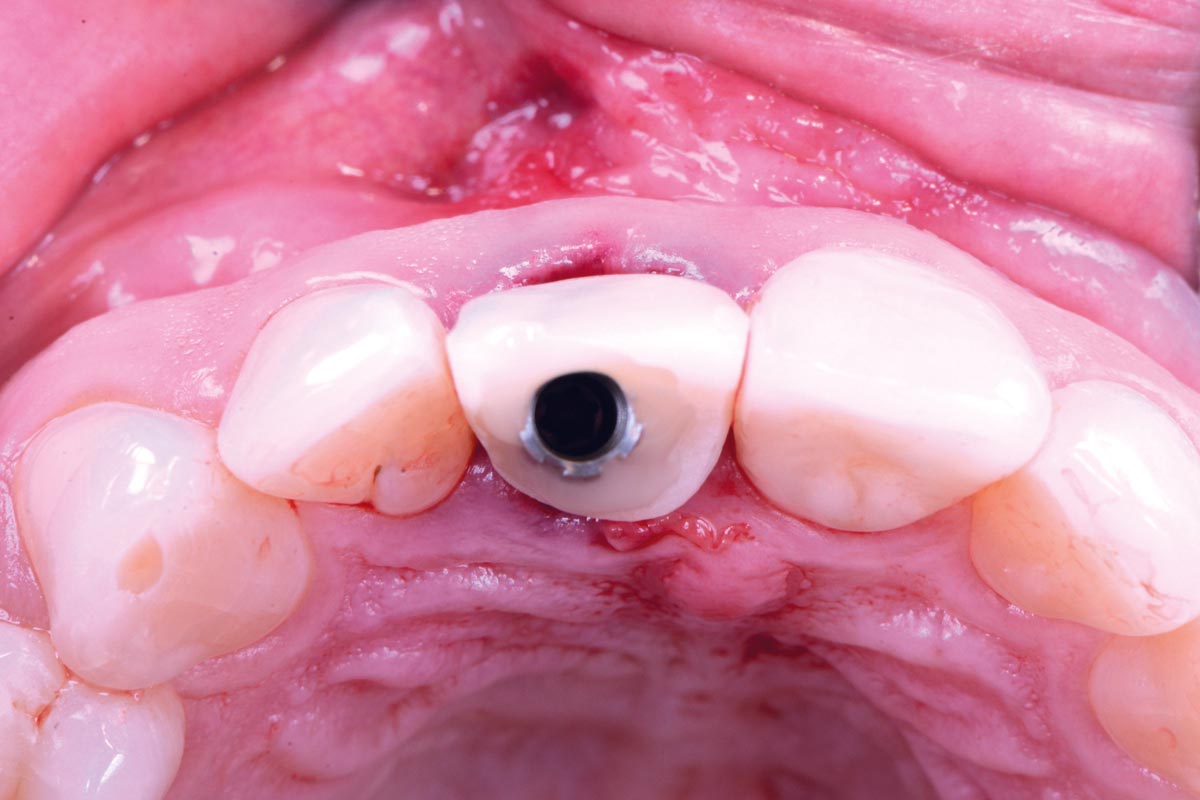

10/30 - Occlusal view – 4 mm placement depthExcellent aesthetic result of buccal augmentation with mucoderm® and maxgraft® after immediate implant placement - 3-years follow-up - Dr. A. Puišys